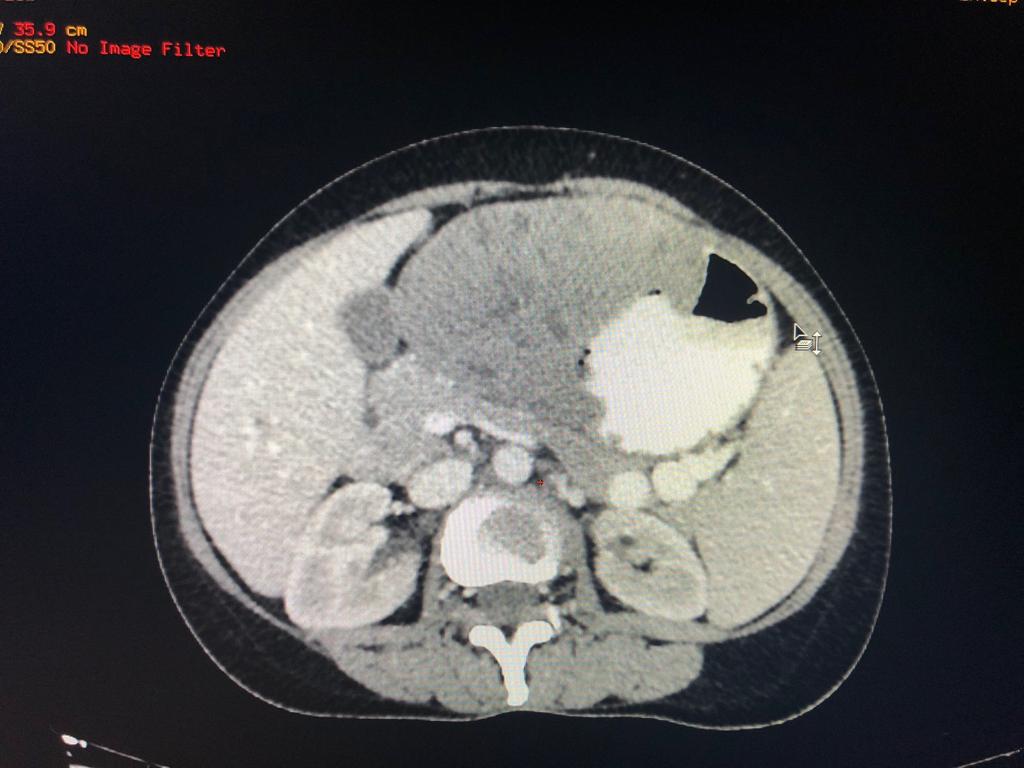

40 year old male with idiopathic chronic pancreatitis presented with intractable pain, sitophobia with severe weight loss (adult male weighs 29 Kg) and history of recurrent episodes of GI bleed. He also has CKD (cr1.7) related to neurogenic bladder. Patient was shifted to us in shock with HB 3 gm % and massive GI bleed. MRI and CT angio showed a large 6x5 cm Pseudoaneurysm in uncinate process of pancreas probably arising from inferior pancreaticoduordenal artery causing hemosuccus pancreas. In view of CKD we chose to tackle aneurysm by direct glue embolisation of aneurysm sac to avoid the high volume contrast of conventional angio (image) Pt was put on NJ feeds in view of severe malnutrition secondary to intractable pain and sitophobia. Post embolisation 2 months later he came back with weight gain of 8 kg and a stable Hb%. His Repeated CT scan showed a persistent intrapancreatic head cyst with dilated pd in body and tail. The aneurysm cavity filled with glue cast has shrunk to almost one fifth the initial size. In view of large duct disease with Pseudoaneurysm we decided to go ahead with a whipple pancreaticoduodenectomy. The post op specimen shows the intrapancreatic cyst and the glue cast of the aneurysm (yellow arrow). His recovery was uneventful and is completely pain free post procedure.